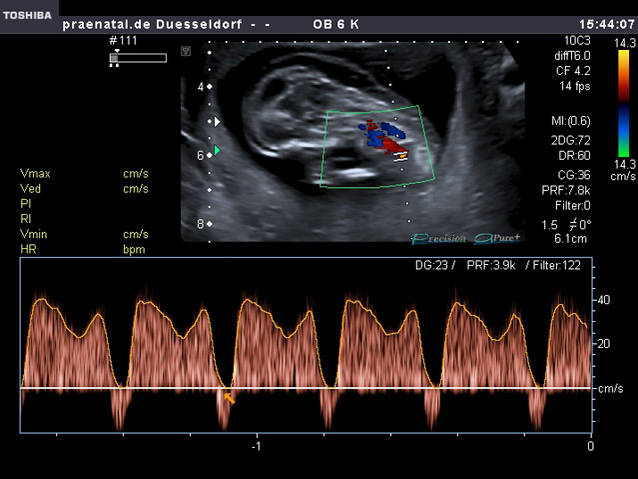

Doppleruntersuchung

Kombination aus der Darstellung von Blutflüssen und von Flussprofilen Bild. Die Flussprofile liefern uns Informationen über die Versorgung der Plazenta, die Herzleistung des Kindes, eine eventuelle Blutarmut oder die Blutverteilung im kindlichen Kreislauf.